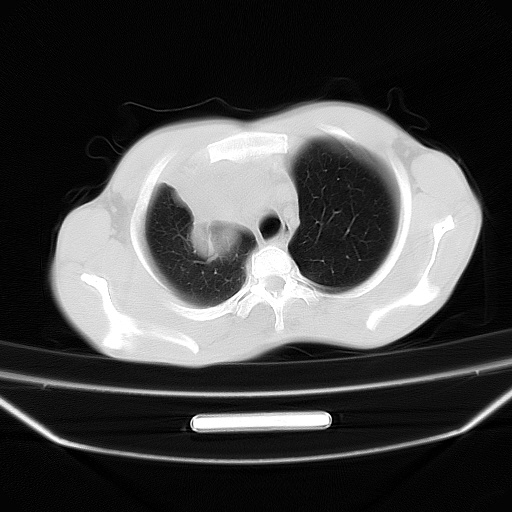

以下是引用zjzjr在2008-7-20 12:57:00的发言:[br]考虑为生殖源性肿瘤(内胚窦瘤),侵袭性胸腺瘤可能性大;右侧少量胸腔积液。

以下是引用xinliheng001在2008-7-20 21:17:00的发言:[br]右纵隔巨大分叶状软组织均质密度肿块,右上肺叶受压明显,纵隔右移、胸膜受累有少量积液和结节样增厚。应增强扫描一定会有更具诊断价值的信息。

以下是引用xinliheng001在2008-7-20 21:17:00的发言:[br]右纵隔巨大分叶状软组织均质密度肿块,右上肺叶受压明显,纵隔右移、胸膜受累有少量积液和结节样增厚。应增强扫描一定会有更具诊断价值的信息。